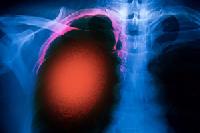

Магнитно-резонансная томография (МРТ):один из самых эффективных методов диагностики заболеваний